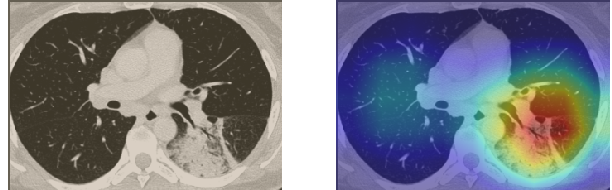

A wide variety of typical and atypical CT abnormalities have been reported for COVID-19 patients in various studies [58, 59]. So, we tested our models on external CT images extracted from these two publications as they feature typical findings of COVID-19 pneumonia marked by specialists. In order to make sure that not any of the extracted images are unintentionally included in our datasets, specifically the COVID19-CT dataset, we use the model trained on the SARS-CoV-2 dataset. First, the InceptionV3 model is employed to classify the extracted CT images. The model is able to correctly classify the given CT images as COVID-19. Second, in order to interpret the model’s generalization capabilities, we apply the Grad-CAM technique to visualize the regions of abnormalities that are considered. By assessing the different CT images in Figure 15, we can see that the model accurately localizes the disease-related regions. Even more interesting is the fact that the model ignores any specific marks in the images like letters and only localizes the COVID-19 related regions. These visual explanations show the success of our models to learn relevant, generic visual features related to COVID-19 and are capable to correctly classify CT images outside the datasets on which they are trained.

Figure 16 shows various CT scans where only one lung is visible. The CT scans are also extracted from the paper [58] and show different CT manifestations of COVID-19 pneumonia marked by red squares. The InceptionV3 model is capable to classify them correctly as COVID-19, although it is trained on CT scans where the entire lung is visible. Intriguingly, when applying Grad-CAM we can see that all regions of abnormalities are accurately localized. This also proves the potential of our model to detect COVID-19 abnormalities in CT images outside the dataset used for training.